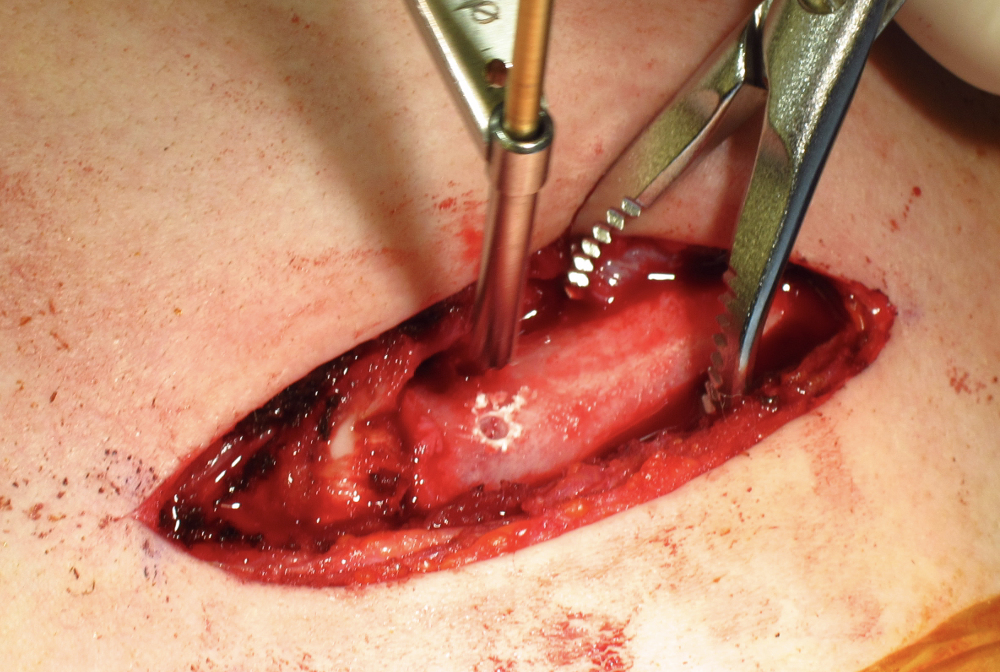

Open reduction of acute posterior sternoclavicular joint dislocation

Drill holes in manubrium and medial clavicle

Figure of 8 suture fixation